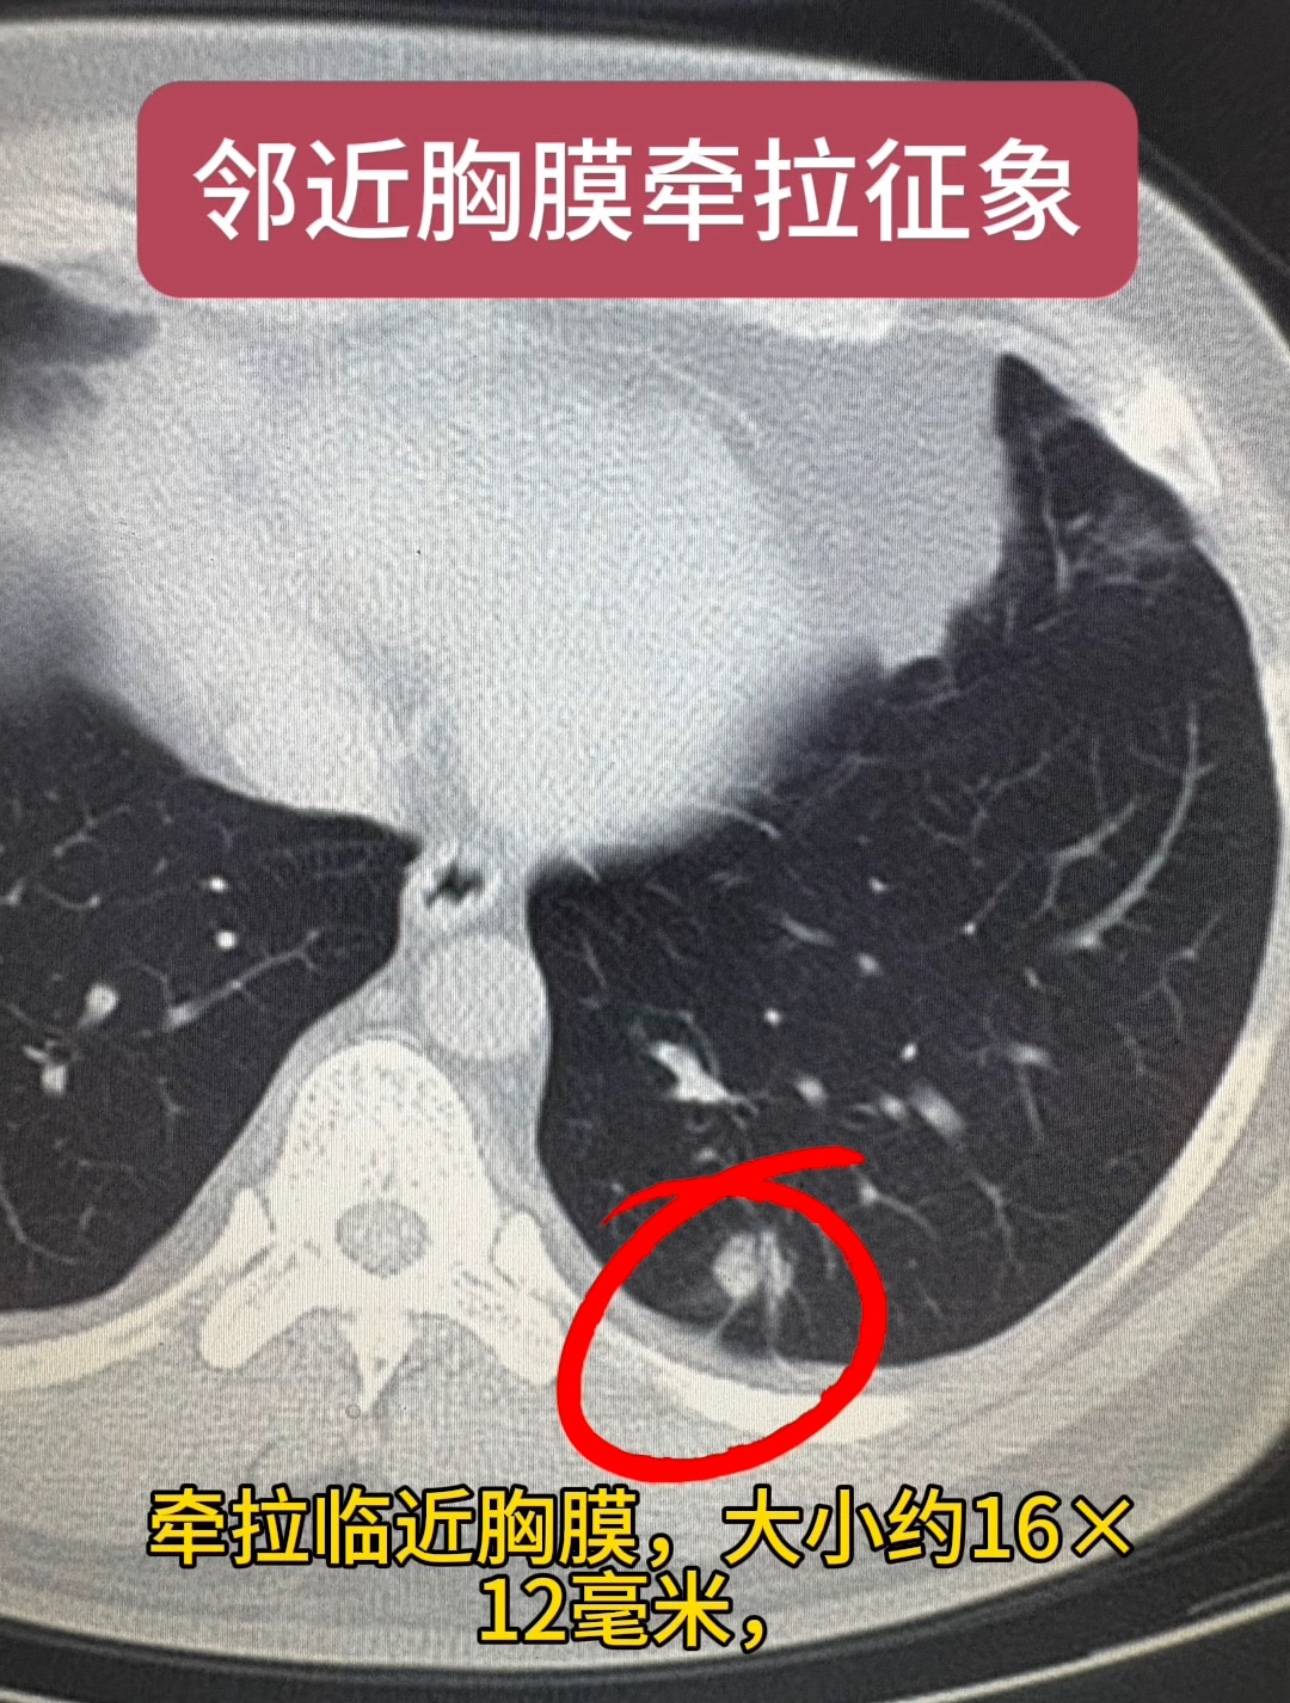

患者男性,34岁,已婚。检查发现肺结节1个月。患者1个月前检查发现左下肺结节,病程中患者无咳嗽咳痰,无胸痛胸闷,牵拉临近胸膜,大小约16×12毫米,考虑为高危倾向你予以抗炎对症治疗,后复查胸部CT发现,左肺下叶后基底段实性结节,较之前变化不明显,术后病理显示为低分化腺癌,术后胸片显示肺膨胀良好。